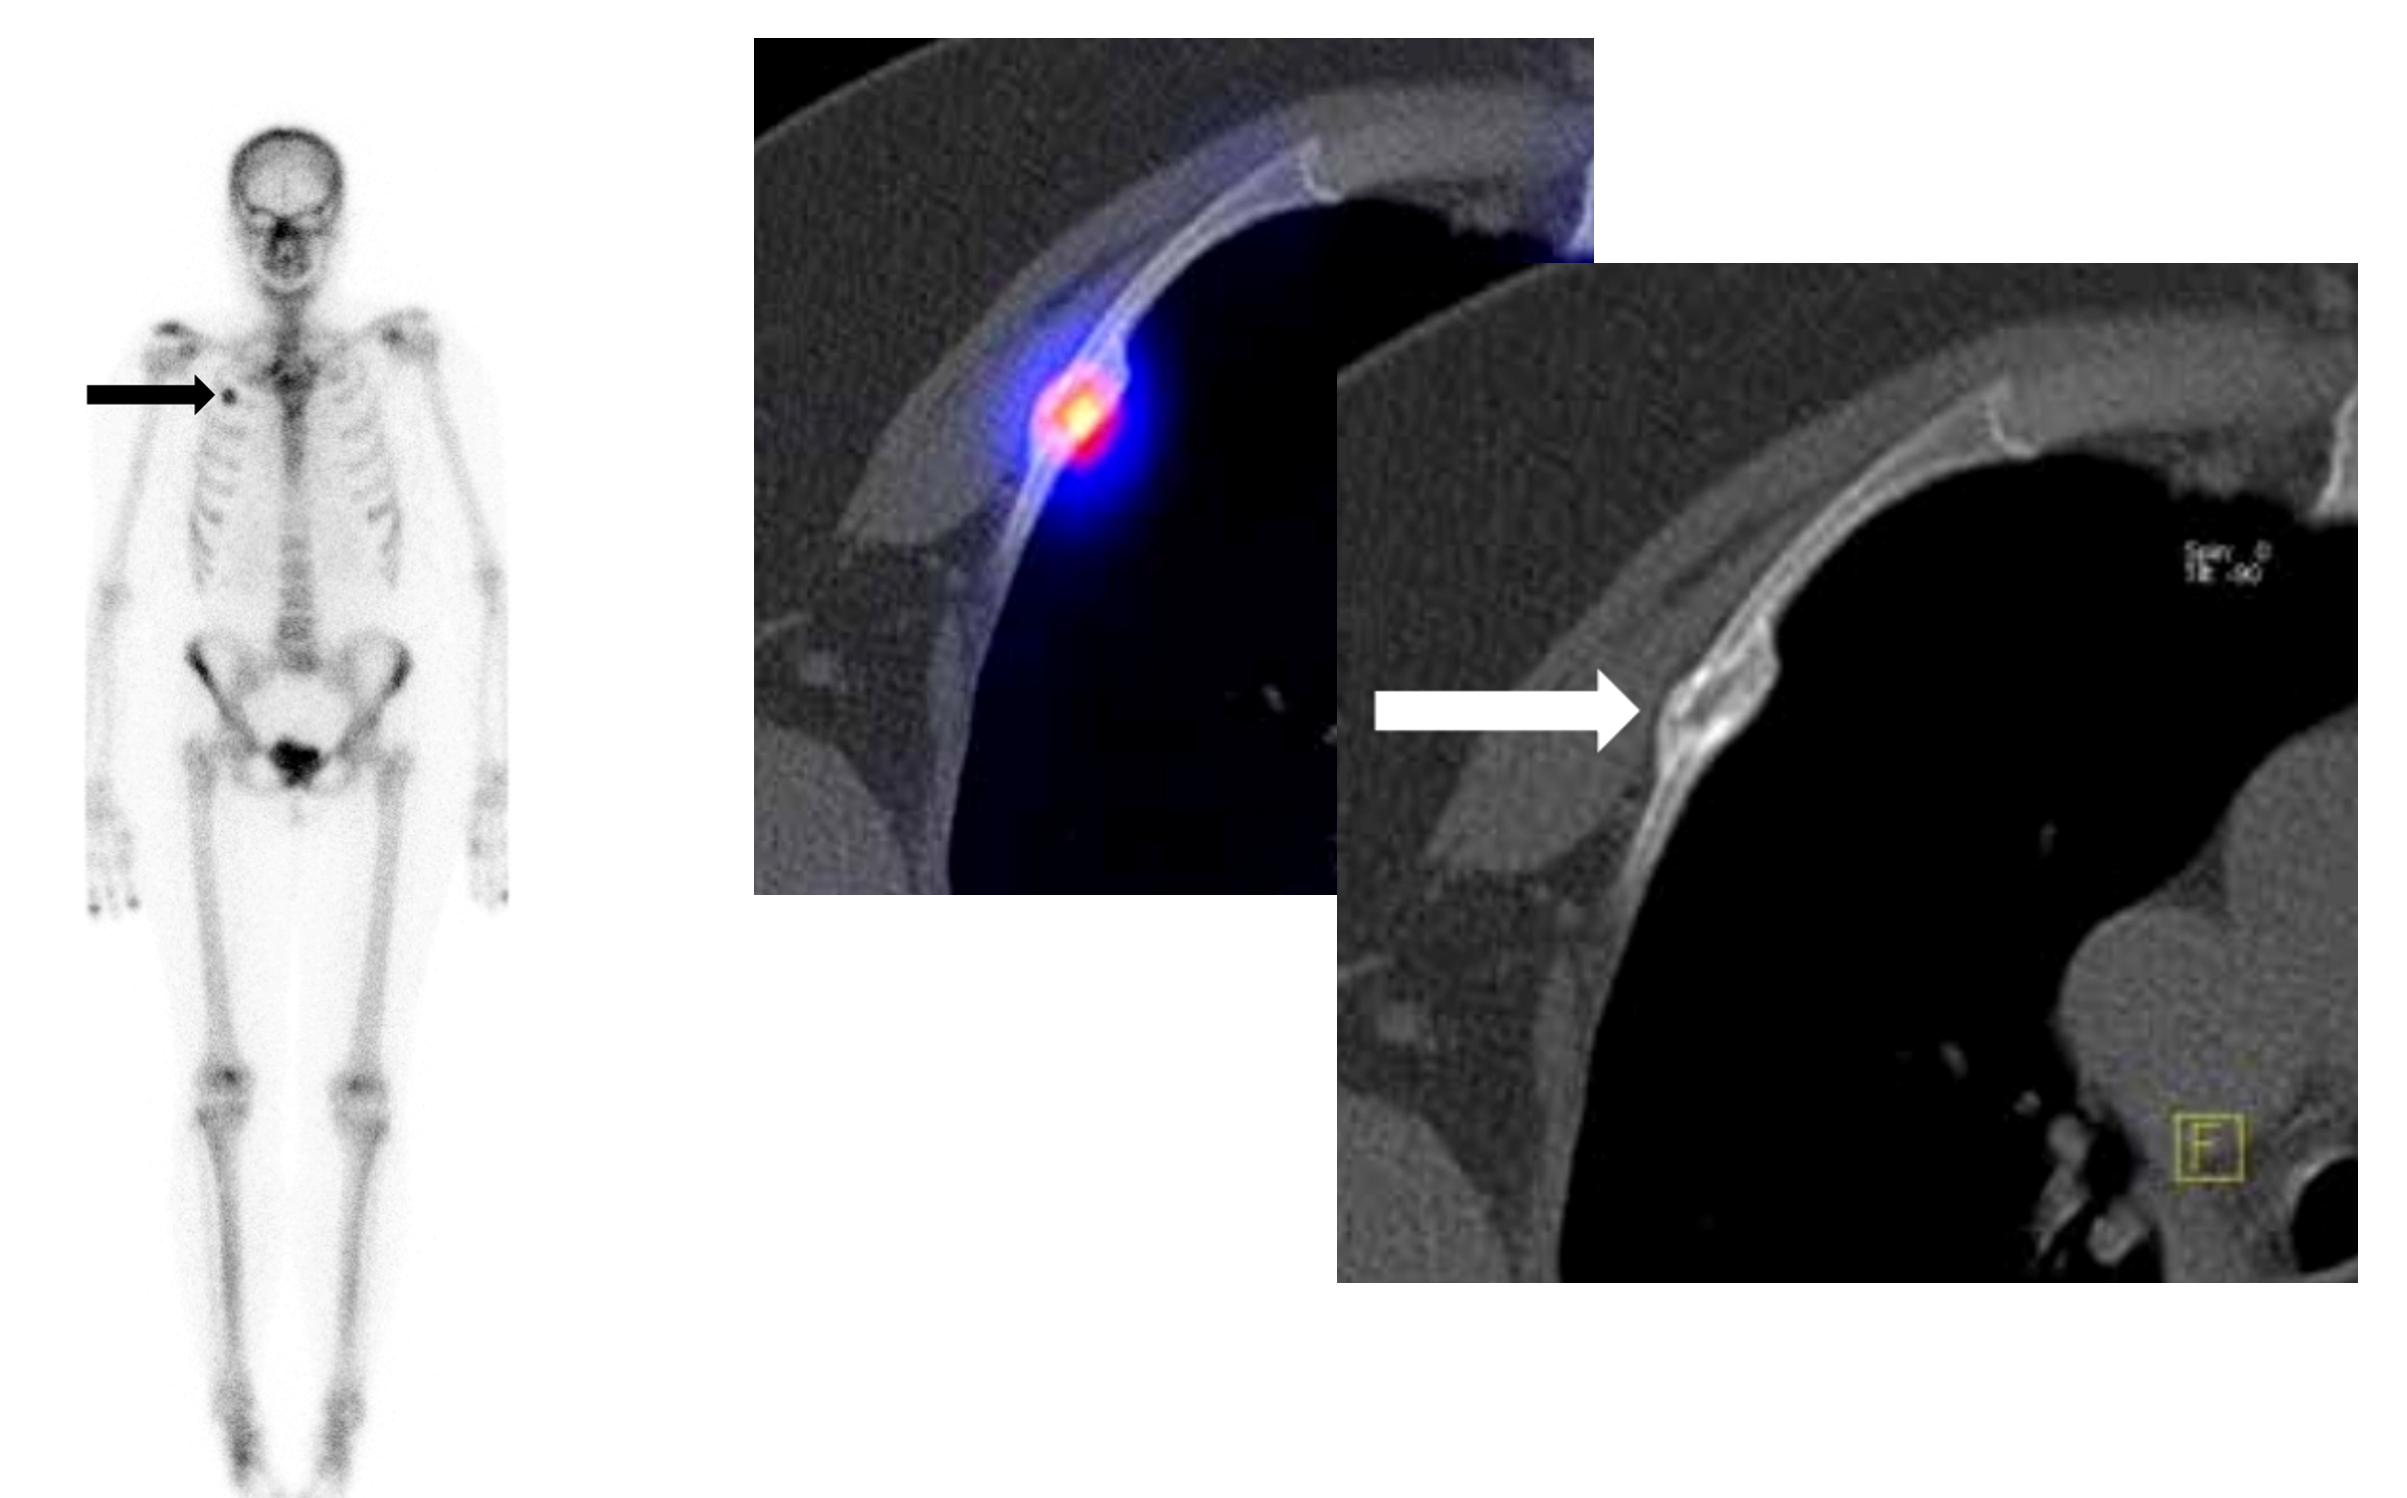

Το Lu-177 PSMA αποτελεί μια στοχευμένη ραδιονουκλιδική θεραπεία για ασθενείς με ορμονοάντοχο μεταστατικό καρκίνο του προστάτη (mCRPC), αξιοποιώντας τη υπερέκφραση του PSMA (Prostate-Specific Membrane Antigen) στα καρκινικά κύτταρα. Προηγείται PSMA PET/CT για ακριβή χαρτογράφηση της νόσου και επιβεβαίωση επαρκούς πρόσληψης του ραδιοφάρμακου. Το Lu-177 PSMA συνδέεται στους PSMA-υποδοχείς, επιτρέποντας στοχευμένη ακτινική δράση υψηλής κυτταροτοξικότητας σε μεταστατικές εστίες οστών και μαλακών μορίων. Η χρήση εξειδικευμένων δοσιμετρικών εργαλείων επιτρέπει την ποσοτική αποτίμηση της δόσης σε κρίσιμα όργανα (π.χ. σιελογόνοι αδένες, νεφροί, μυελός) και στον όγκο, συμβάλλοντας σε εξατομικευμένη θεραπευτική προσέγγιση. Μετά από κάθε κύκλο πραγματοποιείται PSMA PET/CT ή FDG PET/CT (όπου ενδείκνυται), καθώς και στενός αιματολογικός έλεγχος για αξιολόγηση της ανταπόκρισης και των πιθανών τοξικοτήτων. Η θεραπεία έχει αποδειχθεί ιδιαίτερα αποτελεσματική στη μείωση του καρκινικού φορτίου, στη βελτίωση του πόνου, στη μείωση των επιπέδων PSA και στη σημαντική παράταση του προσδόκιμου επιβίωσης σε ασθενείς με εκτεταμένη και ανθεκτική νόσο.

Με τη SPECT‑CT ποσοτικοποίηση υπολογίζουμε απορροφούμενες δόσεις σε όγκους και όργανα‑στόχους (νεφροί, σιελογόνοι, ήπαρ, μυελός κ.ά.). Αυτό:

Με βάση τα σύγχρονα Guidelines όλων των διεθνών ογκολογικών εταιρειών η μεταθεραπευτική απεικόνιση είναι προαπαιτούμενο για την έναρξη-συνέχιση της θεραπείας και το βέλτιστο αποτέλεσμα αυτής.

ΠΟΣΟΤΙΚΗ ΕΚΤΙΜΗΣΗ – ΜΕΤΡΗΣΗ ΟΓΚΟΥ ΝΟΣΟΥ

PSMA‑θετικός καρκίνος προστάτη